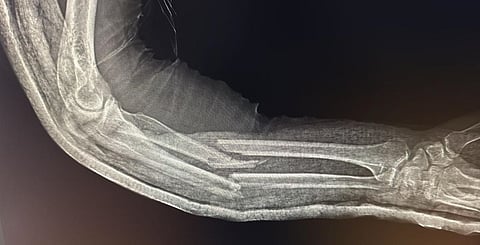

نجح الفريق الطبي في مستشفى ضرما العام عضو تجمع الرياض الصحي الثالث في إجراء عملية جراحية دقيقة لمقيم آسيوي يبلغ من العمر 51 عامًا، وذلك بعد تعرضه لحادث سير أسفر عن كسر مضاعف في عظمتي الساعد الأيمن.

وبعد إجراء الفحوصات والأشعة اللازمة، تقرر التدخل الجراحي العاجل وجرى تنويم المريض وتحضيره للعملية، وأُجريت له جراحة لتثبيت الكسور باستخدام مثبتات عظمية داخلية، وقد تكللت بالنجاح التام.